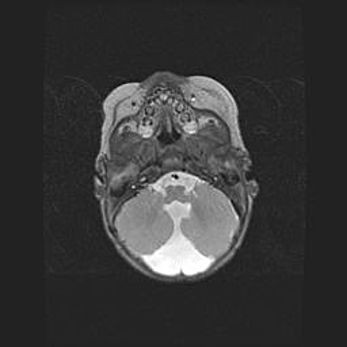

Церебральная ишемия II.

Возраст: 5 дней

Вес: 3400 г

Пол: женский

Окружность головы: 35 см

Срок гестации: 39 недель

Церебральная ишемия – это заболевание, характеризующееся недостаточностью (гипоксией) либо полным прекращением (аноксией) снабжения мозга кислородом по причине закупорки одного или нескольких сосудов. Это приводит к  что метаболическим расстройствам различной степени тяжести в тканях головного мозга, развитию коагуляционных некрозов и гибели нейронов.